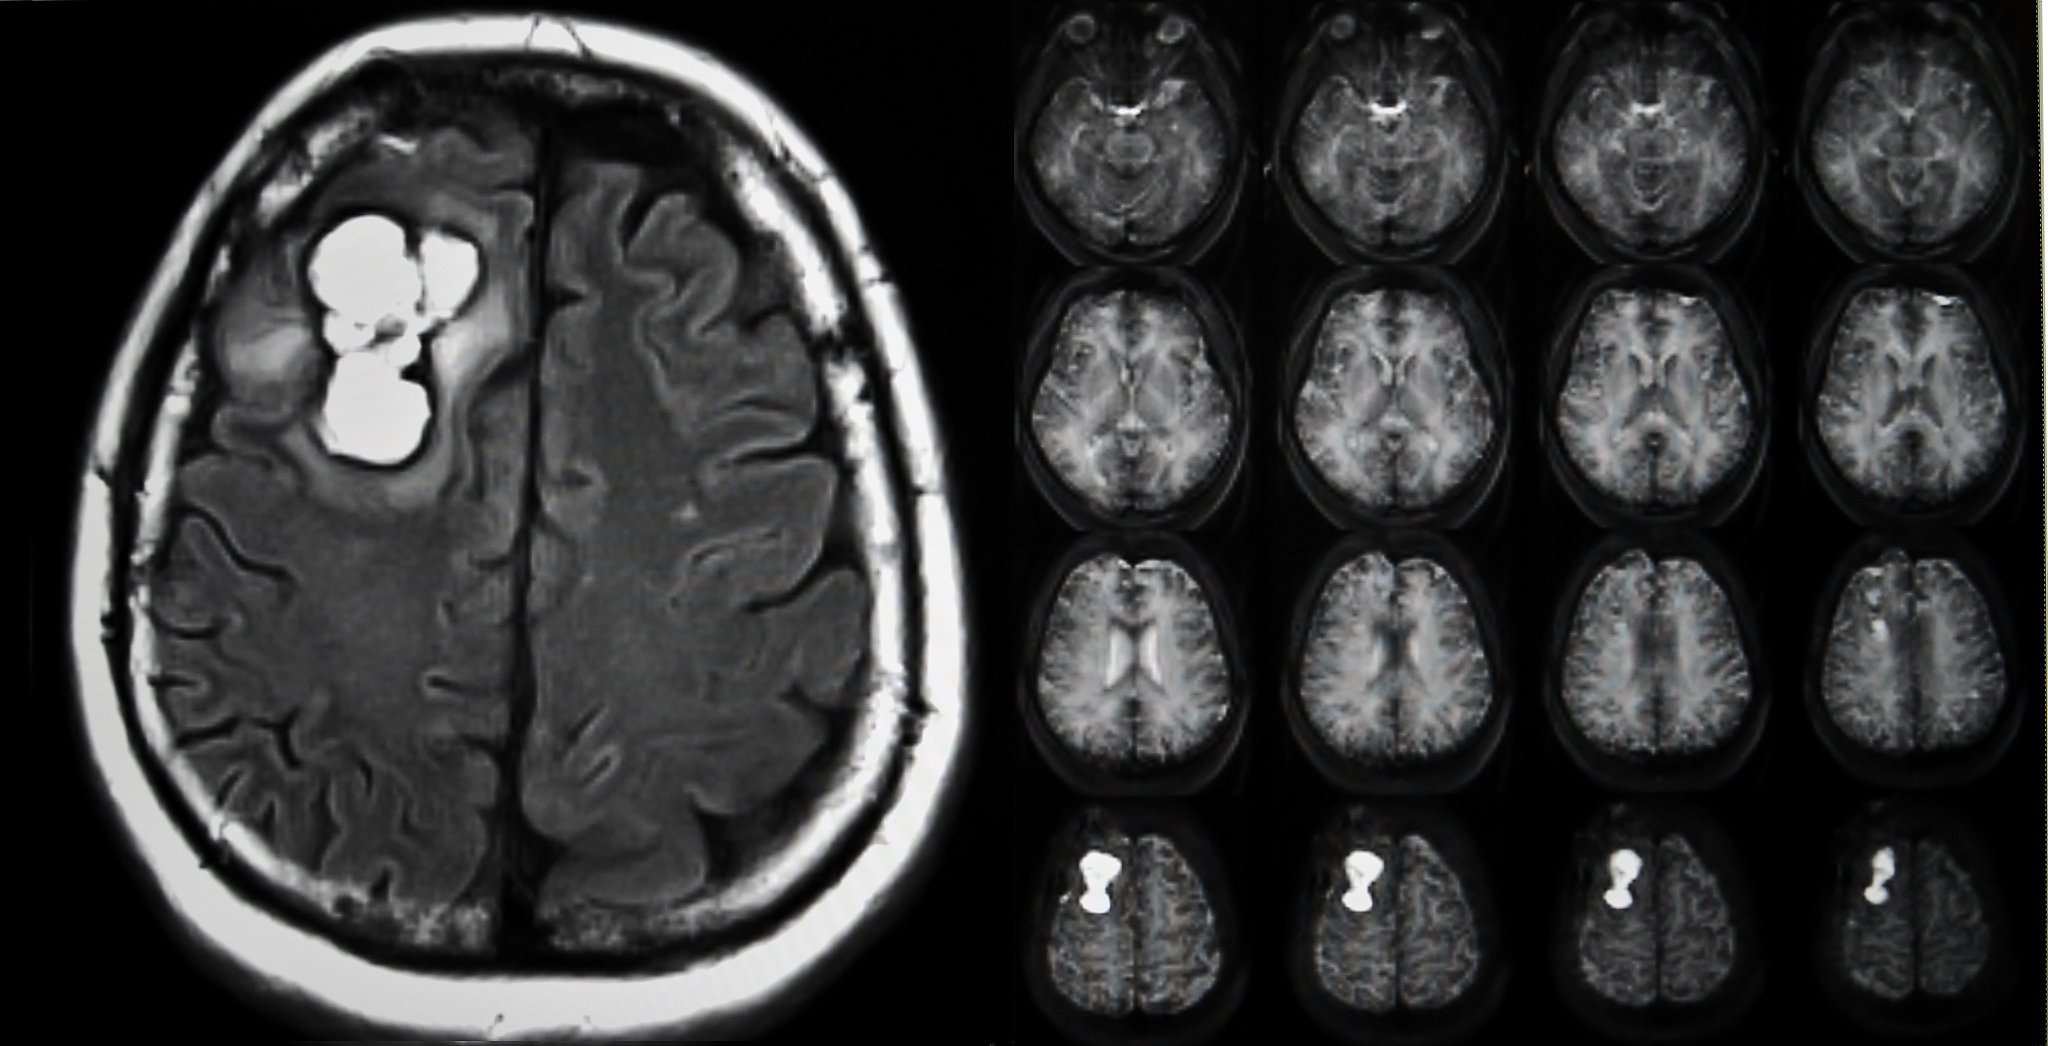

三、腺泡状软组织肉瘤的 MR 表现

在 MR 扫描中,腺泡状软组织肉瘤呈现为 T1 加权图像上的等或低信号,T2 加权图像上的高信号。肿瘤的强化程度较低,强化后呈现为轻度或中度强化。一些研究表明,腺泡状软组织肉瘤在 MR 扫描中的表现与其组织学类型也有关,如纤维性和黏液性腺泡状软组织肉瘤呈现为 T1 加权图像上的低信号,而上皮样和混合型腺泡状软组织肉瘤呈现为 T1 加权图像上的高信号。